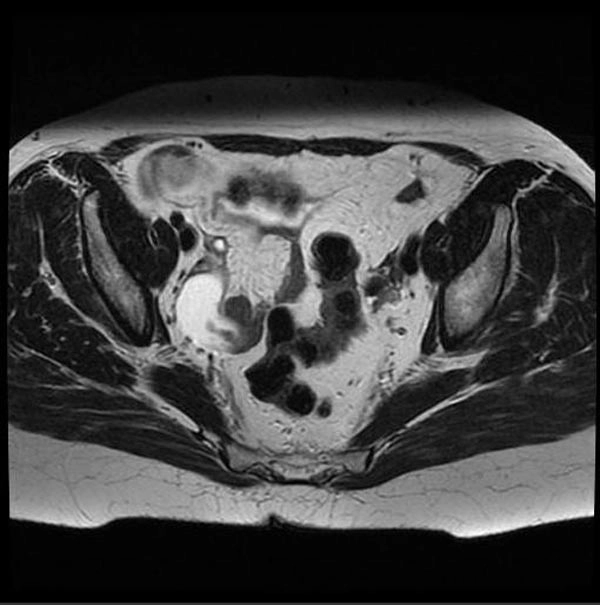

Áp xe vòi trứng - buồng trứng (Tubo-ovarian abscess)